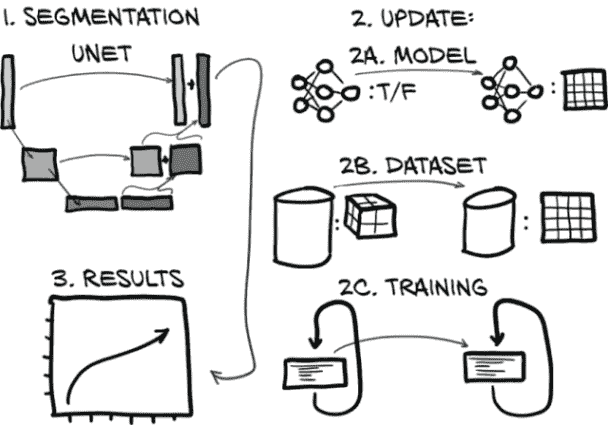

这意味着我们仍然专注于与第十一章相同的图 12.1 的同一部分。但现在我们正在努力使我们的分类模型工作良好而不是只是工作。本章重点讨论如何衡量、量化、表达,然后改进我们的模型执行工作的能力。

图 12.1 我们的端到端肺癌检测项目,重点放在本章的主题上:第 4 步,分类

在前两章中,我们完成了图 13.1 中显示的计划的第 4 步:分类。在本章中,我们不仅要回到上一步,而是回到上两步。我们需要找到一种方法告诉我们的分类器在哪里查找。为此,我们将对原始 CT 扫描进行处理,找出可能是结节的所有内容。这是图中突出显示的第 2 步。为了找到这些可能的结节,我们必须标记看起来可能是结节的体素,这个过程被称为分割。然后,在第十四章中,我们将处理第 3 步,并通过将这幅图像的分割掩模转换为位置注释来提供桥梁。

图 13.1 我们的端到端肺癌检测项目,重点关注本章主题:第 2 步,分割

到本章结束时,我们将创建一个新模型,其架构可以执行像素级标记,或分割。完成这项任务的代码将与上一章的代码非常相似,特别是如果我们专注于更大的结构。我们将要做出的所有更改都将更小且有针对性。正如我们在图 13.2 中看到的,我们需要更新我们的模型(图中的第 2A 步),数据集(2B),以及训练循环(2C),以适应新模型的输入、输出和其他要求。(如果你在图中右侧的步骤 2 中不认识每个组件,不要担心。我们在到达每个步骤时会详细讨论。)最后,我们将检查运行新模型时得到的结果(图中的第 3 步)。

图 13.2 用于分割的新模型架构,以及我们将实施的模型、数据集和训练循环更新

将图 13.2 分解为步骤,我们本章的计划如下: